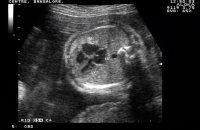

Каждая будущая мама мечтает о том, чтобы увидеть и услышать, как бьётся крохотное сердечко её малыша. Это настоящее чудо, которое позволяет полностью ощутить новую жизнь. Сердцебиение плода является очень важным показателем здоровья малыша.